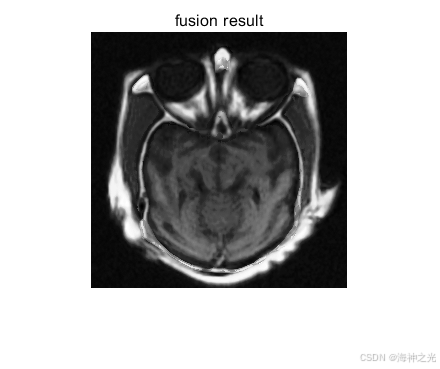

融合规则设计

基带分量采用加权平均或区域能量最大化策略。细节带分量采用绝对值取大或局部对比度规则,例如:

重建与优化

将融合后的基带和细节带通过逆变换重建为最终图像。后处理可能包括对比度增强或去噪。量化评估采用互信息(MI)、结构相似性(SSIM)或边缘保留指数(Q^AB/F)。

⛄三、运行结果